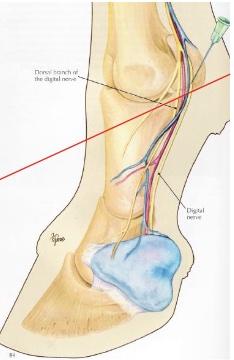

what is desensitized in an abaxial sesamoid nerve block “basisesamoid block”

foot, second phalanx, proximal interphalangeal joint, distopalmar/plantar aspect of proximal phalanx, distal portions of DDFT & SDFT, distal sesamoidean ligaments, digital annular ligament

v shaped area at front of P1 may not be blocked